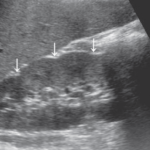

2-Kidney hump

تسمى أيضا Dromedary hump وهي مثل البروز في شكل parenchyma الكلية كسنام الجمل. سماكتها يجب أن تتناسق مع بقية parenchyma المحيطة بدون بروز. هي شائعة تحديدا في الكلية اليسرى وذلك لأن التغير يحدث في مرحلة تطور الجنين وضغط الطحال على الكلية.

في هذه الحالات يجب التأكد من السماكة (متناسقة) و echogenicity (غير مختلفة) و colour Doppler (طبيعية).